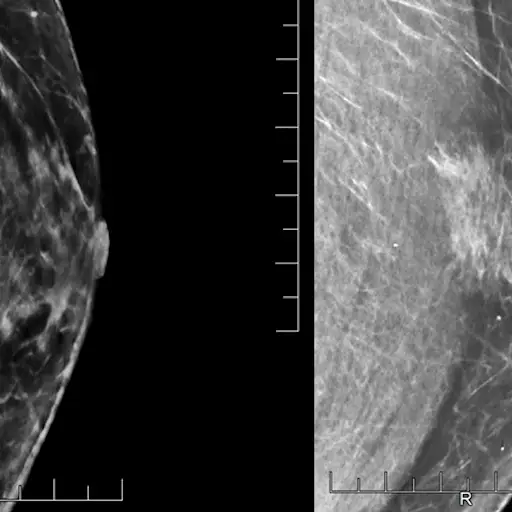

BRCA突变意味着更多的筛查

布莱姆博士说,携带BRCA2基因突变的男性应该和女性一样经常接受筛查。这意味着定期做乳房x光检查。南吉亚医生说,虽然一些携带BRCA突变的女性会接受预防性乳房切除术,但男性通常不会接受。